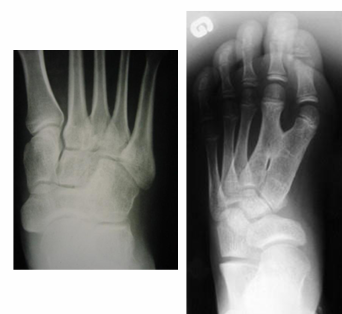

À quoi ressemble la coalition osseuse entre le 1 et 2 métatarse et naviculo-cuboidienne?

A